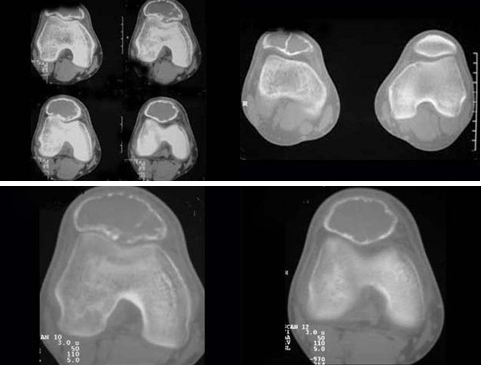

患者,男性,30岁,近2年来感右膝疼痛,活动后加重,2周前由于剧烈运动后,后膝活动受限,右膝压痛明显,有波动感,皮肤稍显红肿,以髌骨部明显,请结合所提供图像,选择最佳选项()

A:纤维性骨皮质缺损

B:非骨化性纤维瘤

C:骨囊肿

D:骨巨细胞瘤

E:动脉瘤样骨囊肿